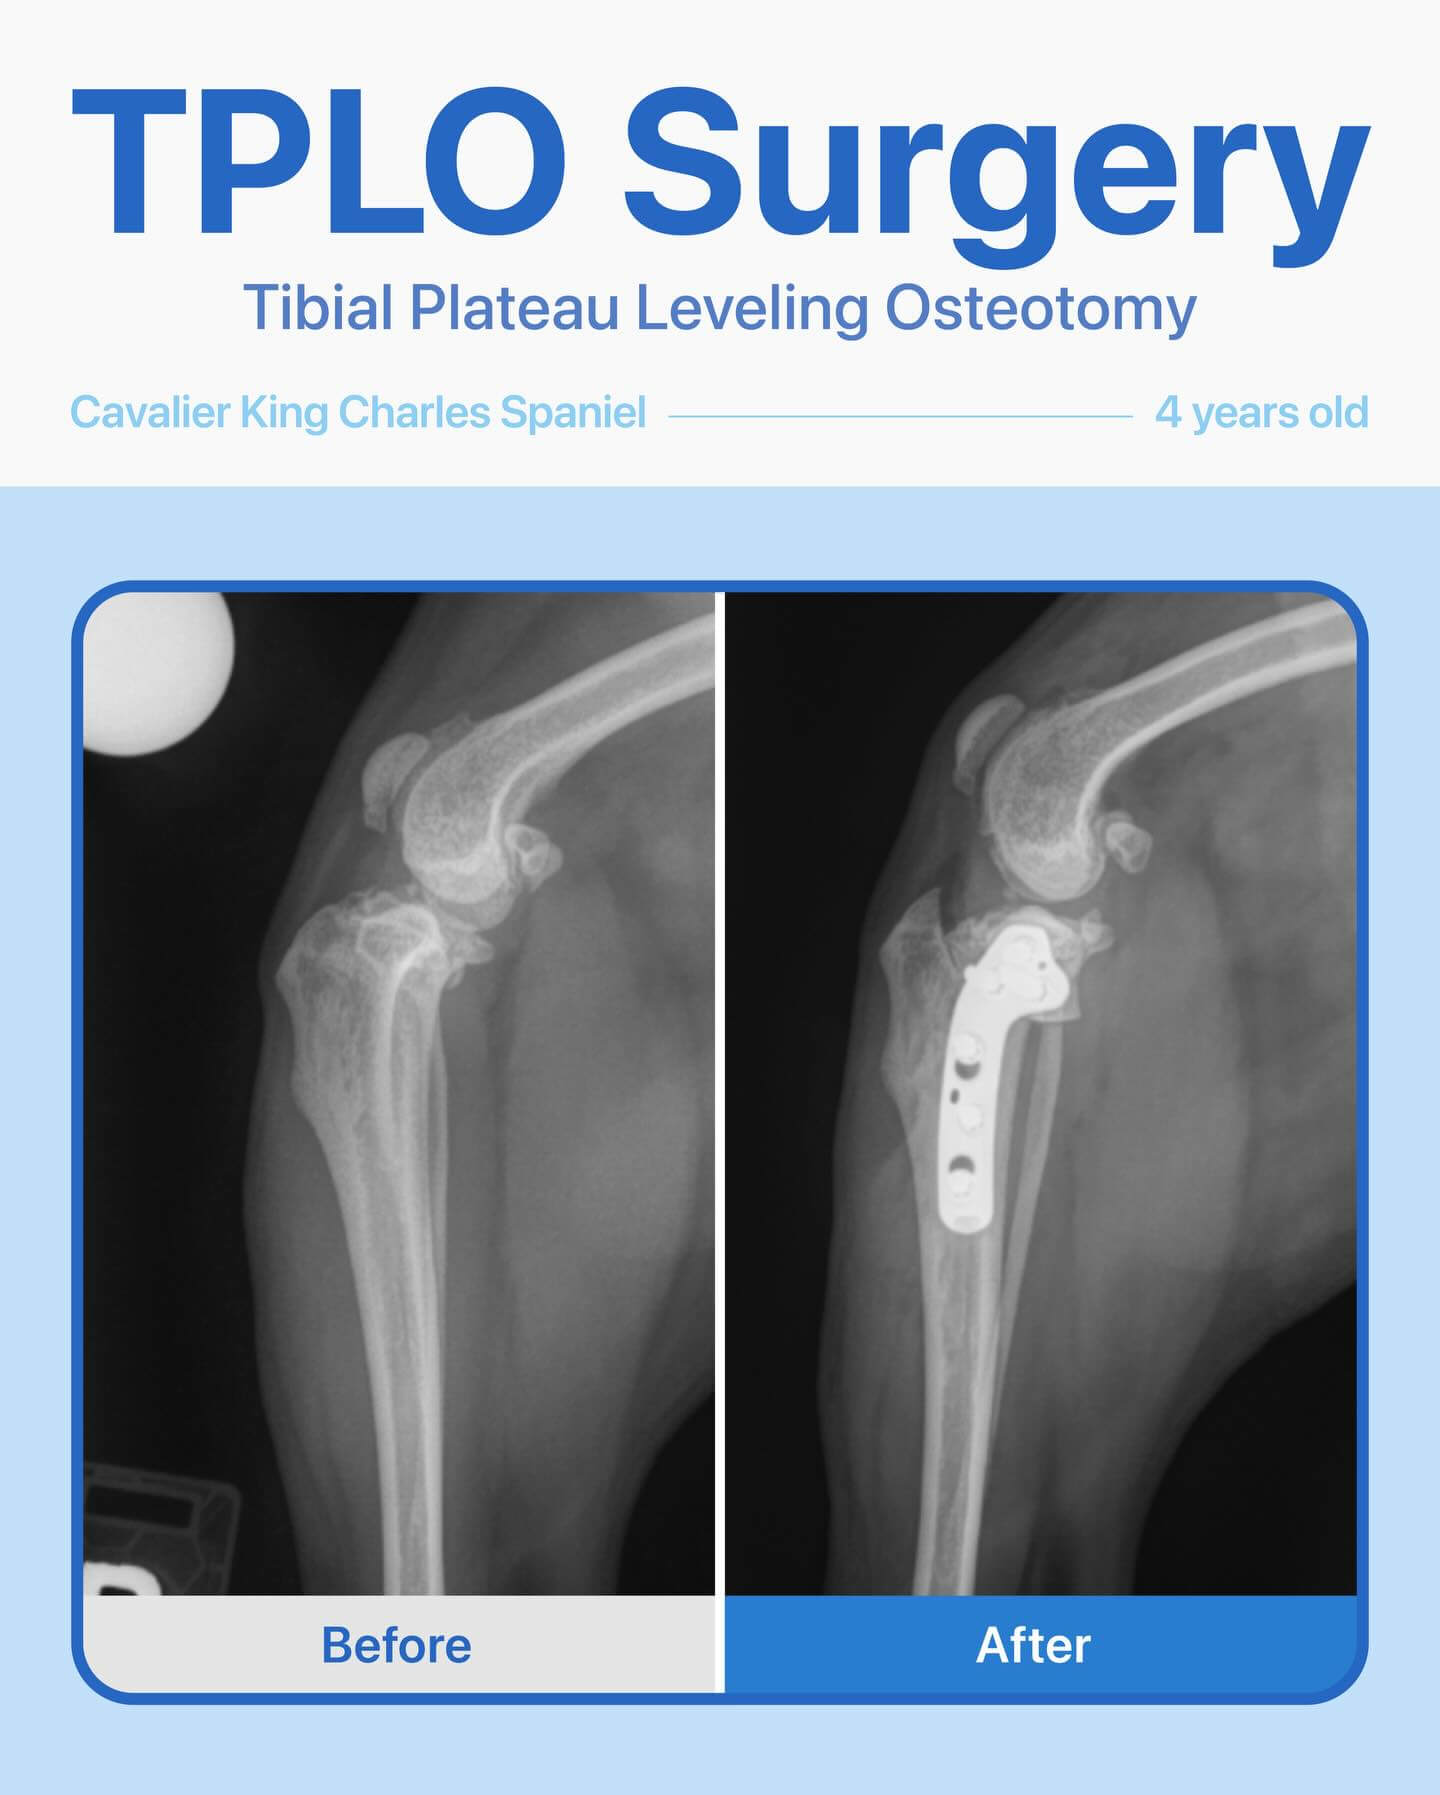

This sweet 4-year-old female Cavalier King Charles Spaniel had been limping on her right back leg for about a year. Her owner noticed the leg looked thinner than the other and that she would yelp when we touched near her hip. After radiographs, we confirmed a cruciate ligament tear, and she underwent a TPLO surgery. The surgery went smoothly, and she’s healing wonderfully! We’re so happy to see her on the road to full recovery.